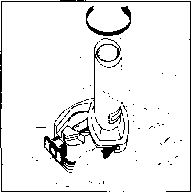

Not: Kapsül bu aşamada parçalanabilir ve küçük jelatin parçacıkları ağzınıza ya da boğazınıza gelebilir. Fakat jelatin yenilebilir nitelikte olduğu için zararlı değildir._ 6. Nefesinizi dışarıya olabildiğince veriniz.

7. İlacı derin bir şekilde hava yollarınıza çekmek

için:

Not: Kapsülün, kapsül bölmesinin üzerindeki alanda dönmesine bağlı olarak bir vızıldama sesi

duymalısınız. Eğer bu vızıldama sesini duymazsanız, kapsül bölmesini açınız ve kapsülün, kapsül bölmesinde sıkışıp sıkışmadığını kontrol ediniz. Daha sonra 7. basamağı tekrarlayınız. Kapsülü sıkıştığı yerden kurtarmak için düğmelere tekrar BASMAYINIZ.

- Ağızlığı ağzınıza yerleştiriniz ve başınızı hafifçe geriye doğru eğiniz.

- Dudaklarınızla ağızlığın etrafım sıkıca sarınız.

- Hızlı, duraksamadan ve alabildiğiniz kadar derin bir nefes alınız.